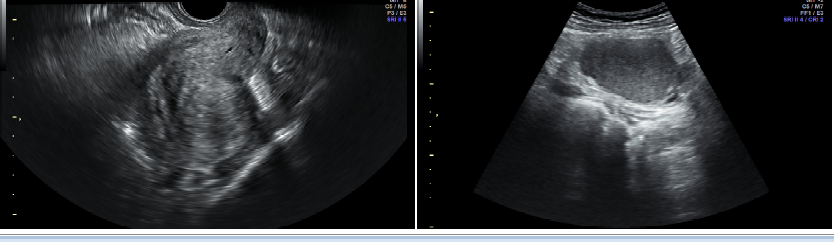

患者,刘某,28岁,G0P0,因“发现左附件肿物3年,痛经进行性加重3月”于2022年2月就诊于北京清华长庚医院妇科。 现病史: 患者平素月经规律,4-5/28天,量中,继发性痛经(+),LMP:2022.01.15。患者8年前开始痛经,可忍受,VAS评分2-3分,偶需服药,痛经时伴恶心、腹泻,无尿频尿急,3年前就诊我院,妇科彩超提示子宫腺肌症、双卵巢非纯囊性包块,右侧大小约2.7cm×2.2cm,左侧大小约4.4cm×3.0cm;盆腔核磁提示:子宫腺肌瘤;双侧巧克力囊肿,左侧较大;右侧输卵管积水?查CA-125:181.5 U/ml,建议手术治疗,患者考虑近期生育,予以口服中成药对症治疗,效果欠佳。近3月患者出现痛经加重,口服止疼药逐渐加量至经期每天2片,VAS评分6分。2022年2月复查彩超提示左卵巢大小7.5cm×5.7cm×5.6cm,内可见非纯囊性包块,大小约6.4cm×5.0cm×4.9cm,内可见密集光点回声,建议手术治疗,门诊以“左侧卵巢囊肿、子宫腺肌症”收入院。 既往史: 2017年因外伤行颅骨骨折手术。余(-) 月经婚育史: 月经初潮14岁,4-5/28天,量多,痛经中重度,需口服止疼药。已婚,G0P0,有生育计划。 家族史: 无特殊 专科查体: 外阴(-); 阴道:已婚未产型,分泌物不多; 宫颈:光,触血阴性; 子宫:前位,稍增大,无压痛; 三合诊:左侧附件区可触及一囊性肿物,直径约6cm,活动度差,压痛(-),右附件区未及明显异常,子宫直肠陷凹可及触痛结节,直径1cm。 辅助检查: TVS(2019-1-20,我院): 子宫前位,大小6.3cm×6.1cm×4.9cm,形态饱满,轮廓尚规整,肌层增厚回声不均匀,内可见多发短线样强回声,后伴栅栏样声影,以后壁为著,前壁厚约1.3cm,后壁厚约4.5cm。子宫内膜厚0.7cm,回声均匀。 右卵巢大小2.4cm×2.3cm×2.1cm,内可见非纯囊性包块,大小约2.7cm×2.2cm,内可见密集光点回声,囊壁可见血流信号。左卵巢大小7.6cm×5.4cm×4.8cm,内可见非纯囊性包块,大小约4.4cm×3.0cm×3.9cm,内可见密集光点回声,囊壁可见血流信号。[超声提示]:子宫腺肌症,双卵巢非纯囊性包块。 2019-1-16 CA125 181.5U/ml 2019-1-25 盆腔核磁提示:子宫腺肌瘤;双侧巧克力囊肿,左侧较大;右侧输卵管积水? TVS(2022-1-19,我院): [超声所见]:子宫前位,大小5.6cm×6.3cm×5.7cm,形态饱满,轮廓尚规整,肌层增厚回声不均匀,内可见多发短线样强回声,后伴栅栏样声影,以后壁为著,前壁厚1.0cm,后壁厚4.3cm,子宫内膜厚0.6cm,回声均匀。右卵巢大小3.3cm×2.4cm×1.8cm。左卵巢大小7.5cm×5.7cm×5.6cm,内可见非纯囊性包块,大小约6.4cm×5.0cm×4.9cm,内可见密集光点回声,囊壁可见血流信号。[超声提示]:子宫腺肌症,左卵巢非纯囊性包块。 2022-1-23 CA125 217.4U/ml AMH:2.07mg/ml